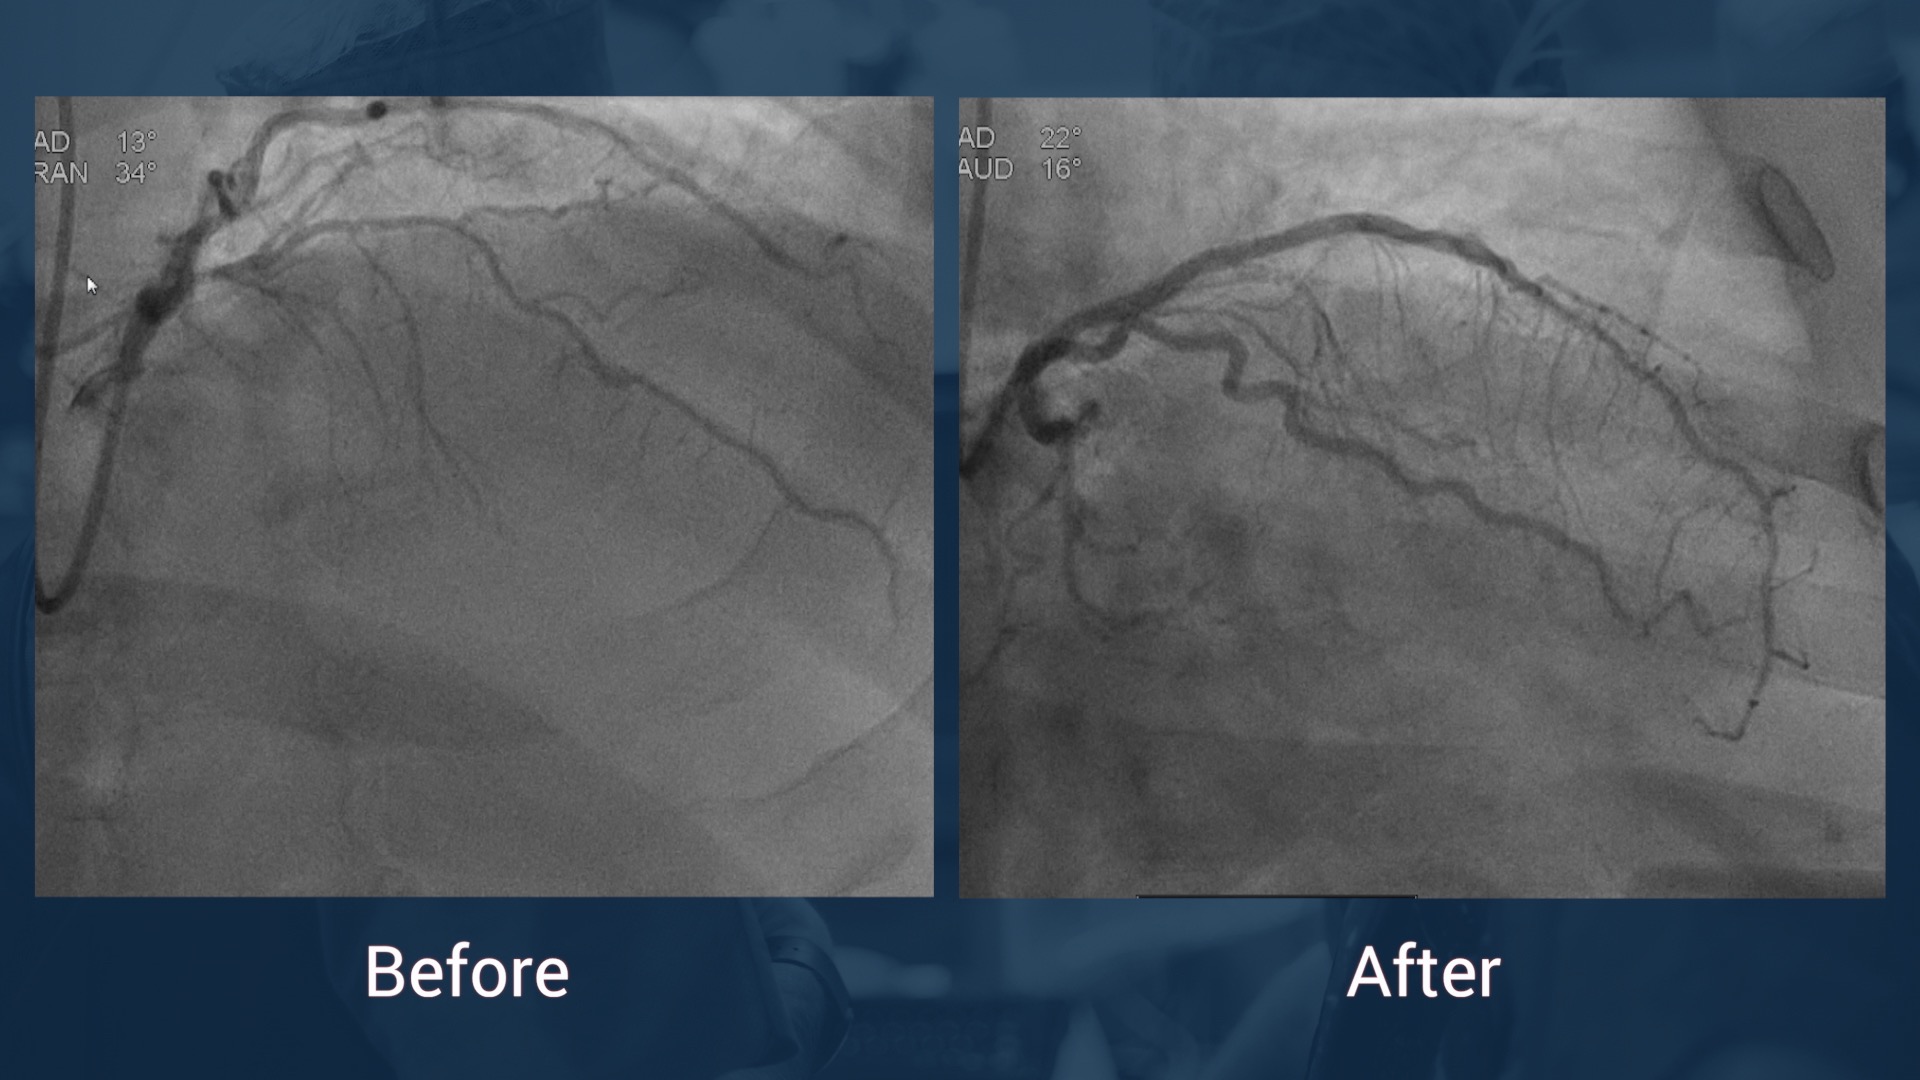

•Today 2nd attempt at CTO RAC

•Antegrade dissection rentry (ADR) technique

•CrossBoss /Stingray

•DES in mid-LAD